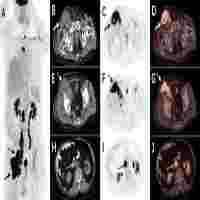

| Abstract | Purpose: We investigated the utility of a new baseline PET parameter expressing lesion dissemination and metabolic parameters for predicting progression-free survival (PFS) and pathologic grade in follicular lymphoma (FL). Methods: Baseline 18F-FDG PET/CT images of 126 patients with grade 1-3A FL were retrospectively analysed. A novel PET/CT parameter characterizing lesion dissemination, the distance between two lesions that were furthest apart (Dmax), was calculated. The total metabolic tumor volume and total lesion glycolysis (TLG) were computed by using the 41% maximum standardized uptake value (SUVmax) thresholding method. Results: The 5-year PFS rate was 51.9% for all patients. In the multivariate analysis, high Dmax [P=0.046; hazard ratio (HR)=2.877], high TLG (P=0.004; HR=3.612), and elevated serum lactate dehydrogenase (P=0.041; HR=2.287) were independent predictors of PFS. A scoring system for prognostic stratification was established based on these three adverse factors, and patients were classified into three risk categories: low-risk (0-1 factor, n=75), intermediate-risk (2 adverse factors, n=29), and high-risk (3 adverse factors, n=22). Patients in the high-risk group had shorter 3-year PFS (21.7%) than those in the low- and intermediate-risk groups (90.6% and 44.6%, respectively) (P<0.001). The C-index of our scoring system for PFS (0.785) was superior to the predictive capability of the Follicular Lymphoma International Prognostic Index (FLIPI), FLIPI2, and PRIMA-Prognostic Index (C-index: 0.628-0.701). The receiver operating characteristic curves and decision curve analysis demonstrated that the scoring system had better differentiation and clinical utility than these existing indices. In addition, the median SUVmax was significantly higher in the grade 3A (36 cases) than in grade 1-2 FL (90 cases) [median: 13.63 vs. 11.45, P = 0.013], but substantial overlap existed (range: 2.25-39.62 vs.3.17-39.80 ). Conclusion: TLG and Dmax represent two complementary aspects of the disease, capturing the tumor burden and lesion dissemination. TLG and Dmax are promising metrics for identifying patients at high-risk of progression or relapse. Additionally, SUVmax seems to have some value for distinguishing grade 3A from low-grade FL but cannot substitute for biopsy. |